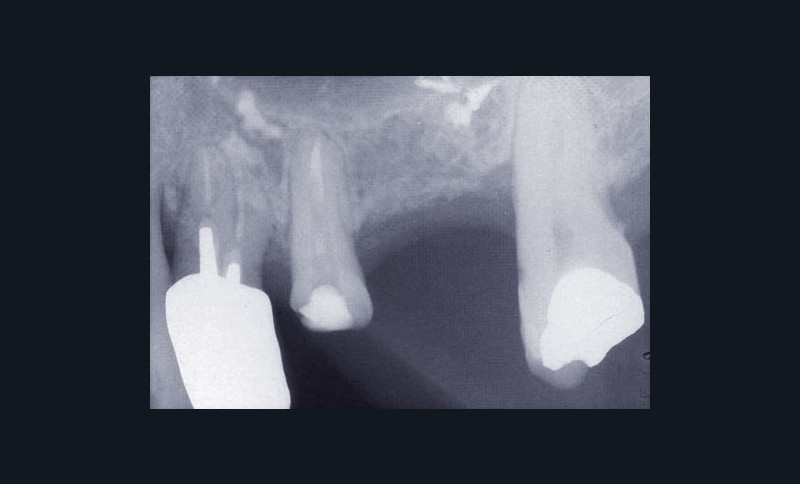

Les examens cliniques et radiographiques montrent une parodontite chronique généralisée (fig. 1a à m).

Nous décidons d’entreprendre une thérapeutique initiale parodontale classique dans tous les secteurs, y compris l’extraction de 24, un bridge de 45 à 48 avec 46 en pontique, un bridge complet de contention de 17 à 27 sur 11 piliers dentaires et une greffe épithélio-conjonctive sur 31. Cette dernière ne sera jamais réalisée. Le bridge maxillaire permettra de réduire le surplomb antérieur et d’améliorer le sourire de la patiente, ce qui constitue l’une de ses demandes.